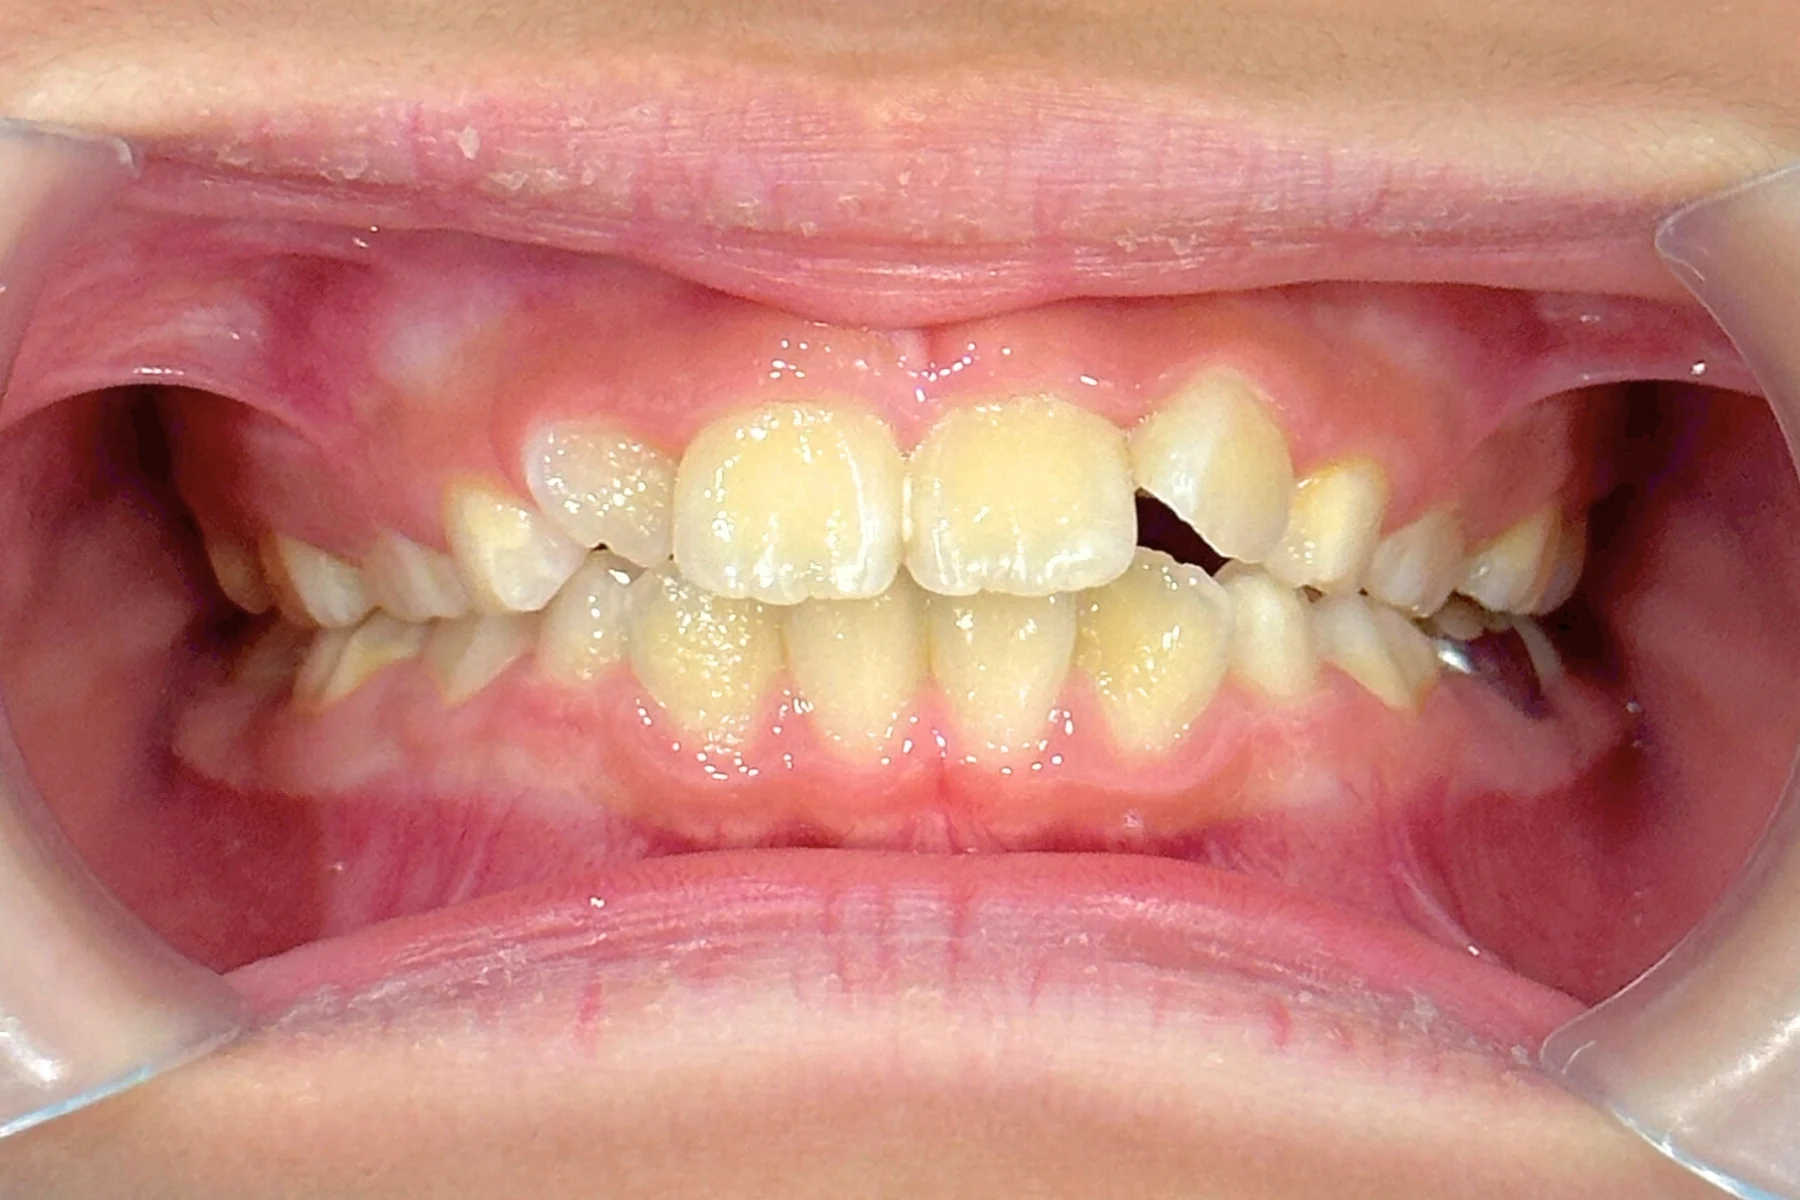

4. 矯正完成:歷經1年5個月的矯正,牙齒排列已明顯整齊,並改善咬合問題。

兒童隱適美_術後